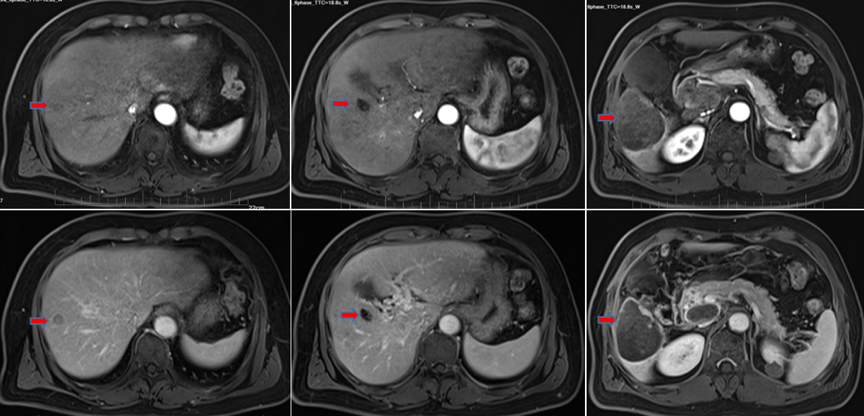

2022年3月9日复查MRI,可见门脉后方肿大淋巴结、腹膜后肿大淋巴无活性且已接近消失,肝右叶肿瘤无明显活性,门脉右支癌栓消退再通(图8);总体评价为完全缓解(CR)。

图8.2022年3月9日复查MRI